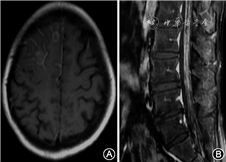

增强核磁共振是影像学诊断脑膜癌病的主要方法之一,主要表现包括:(1)软脑(脊)膜弥漫性或者多发性增厚伴强化;(2)软脑(脊)膜局部结节状强化;(3)多发颅神经根和(或)多发脊神经根增粗伴强化;(4)脑积水;(5)也可以表现为脑白质脱髓鞘和脑梗死等的影像学改变(图3)。脑膜癌病很少与脑实质转移同时出现,可能与两种转移形式的途径与机制不同有关。但应注意的是,颅内感染性疾病(结核、真菌或细菌感染)、结节病、自发性低颅压、头颅外伤、颅脑手术等疾病的患者行头颅磁共振增强检查时,也可能出现脑膜的线型强化。